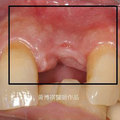

植入人工牙根 瀏覽39 推薦0

齒顎骨僅0.2mm 瀏覽38 推薦0